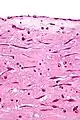

| Micrograph of an atrial myxoma. H&E stain. | |

Atrial myxoma. H&E stain.